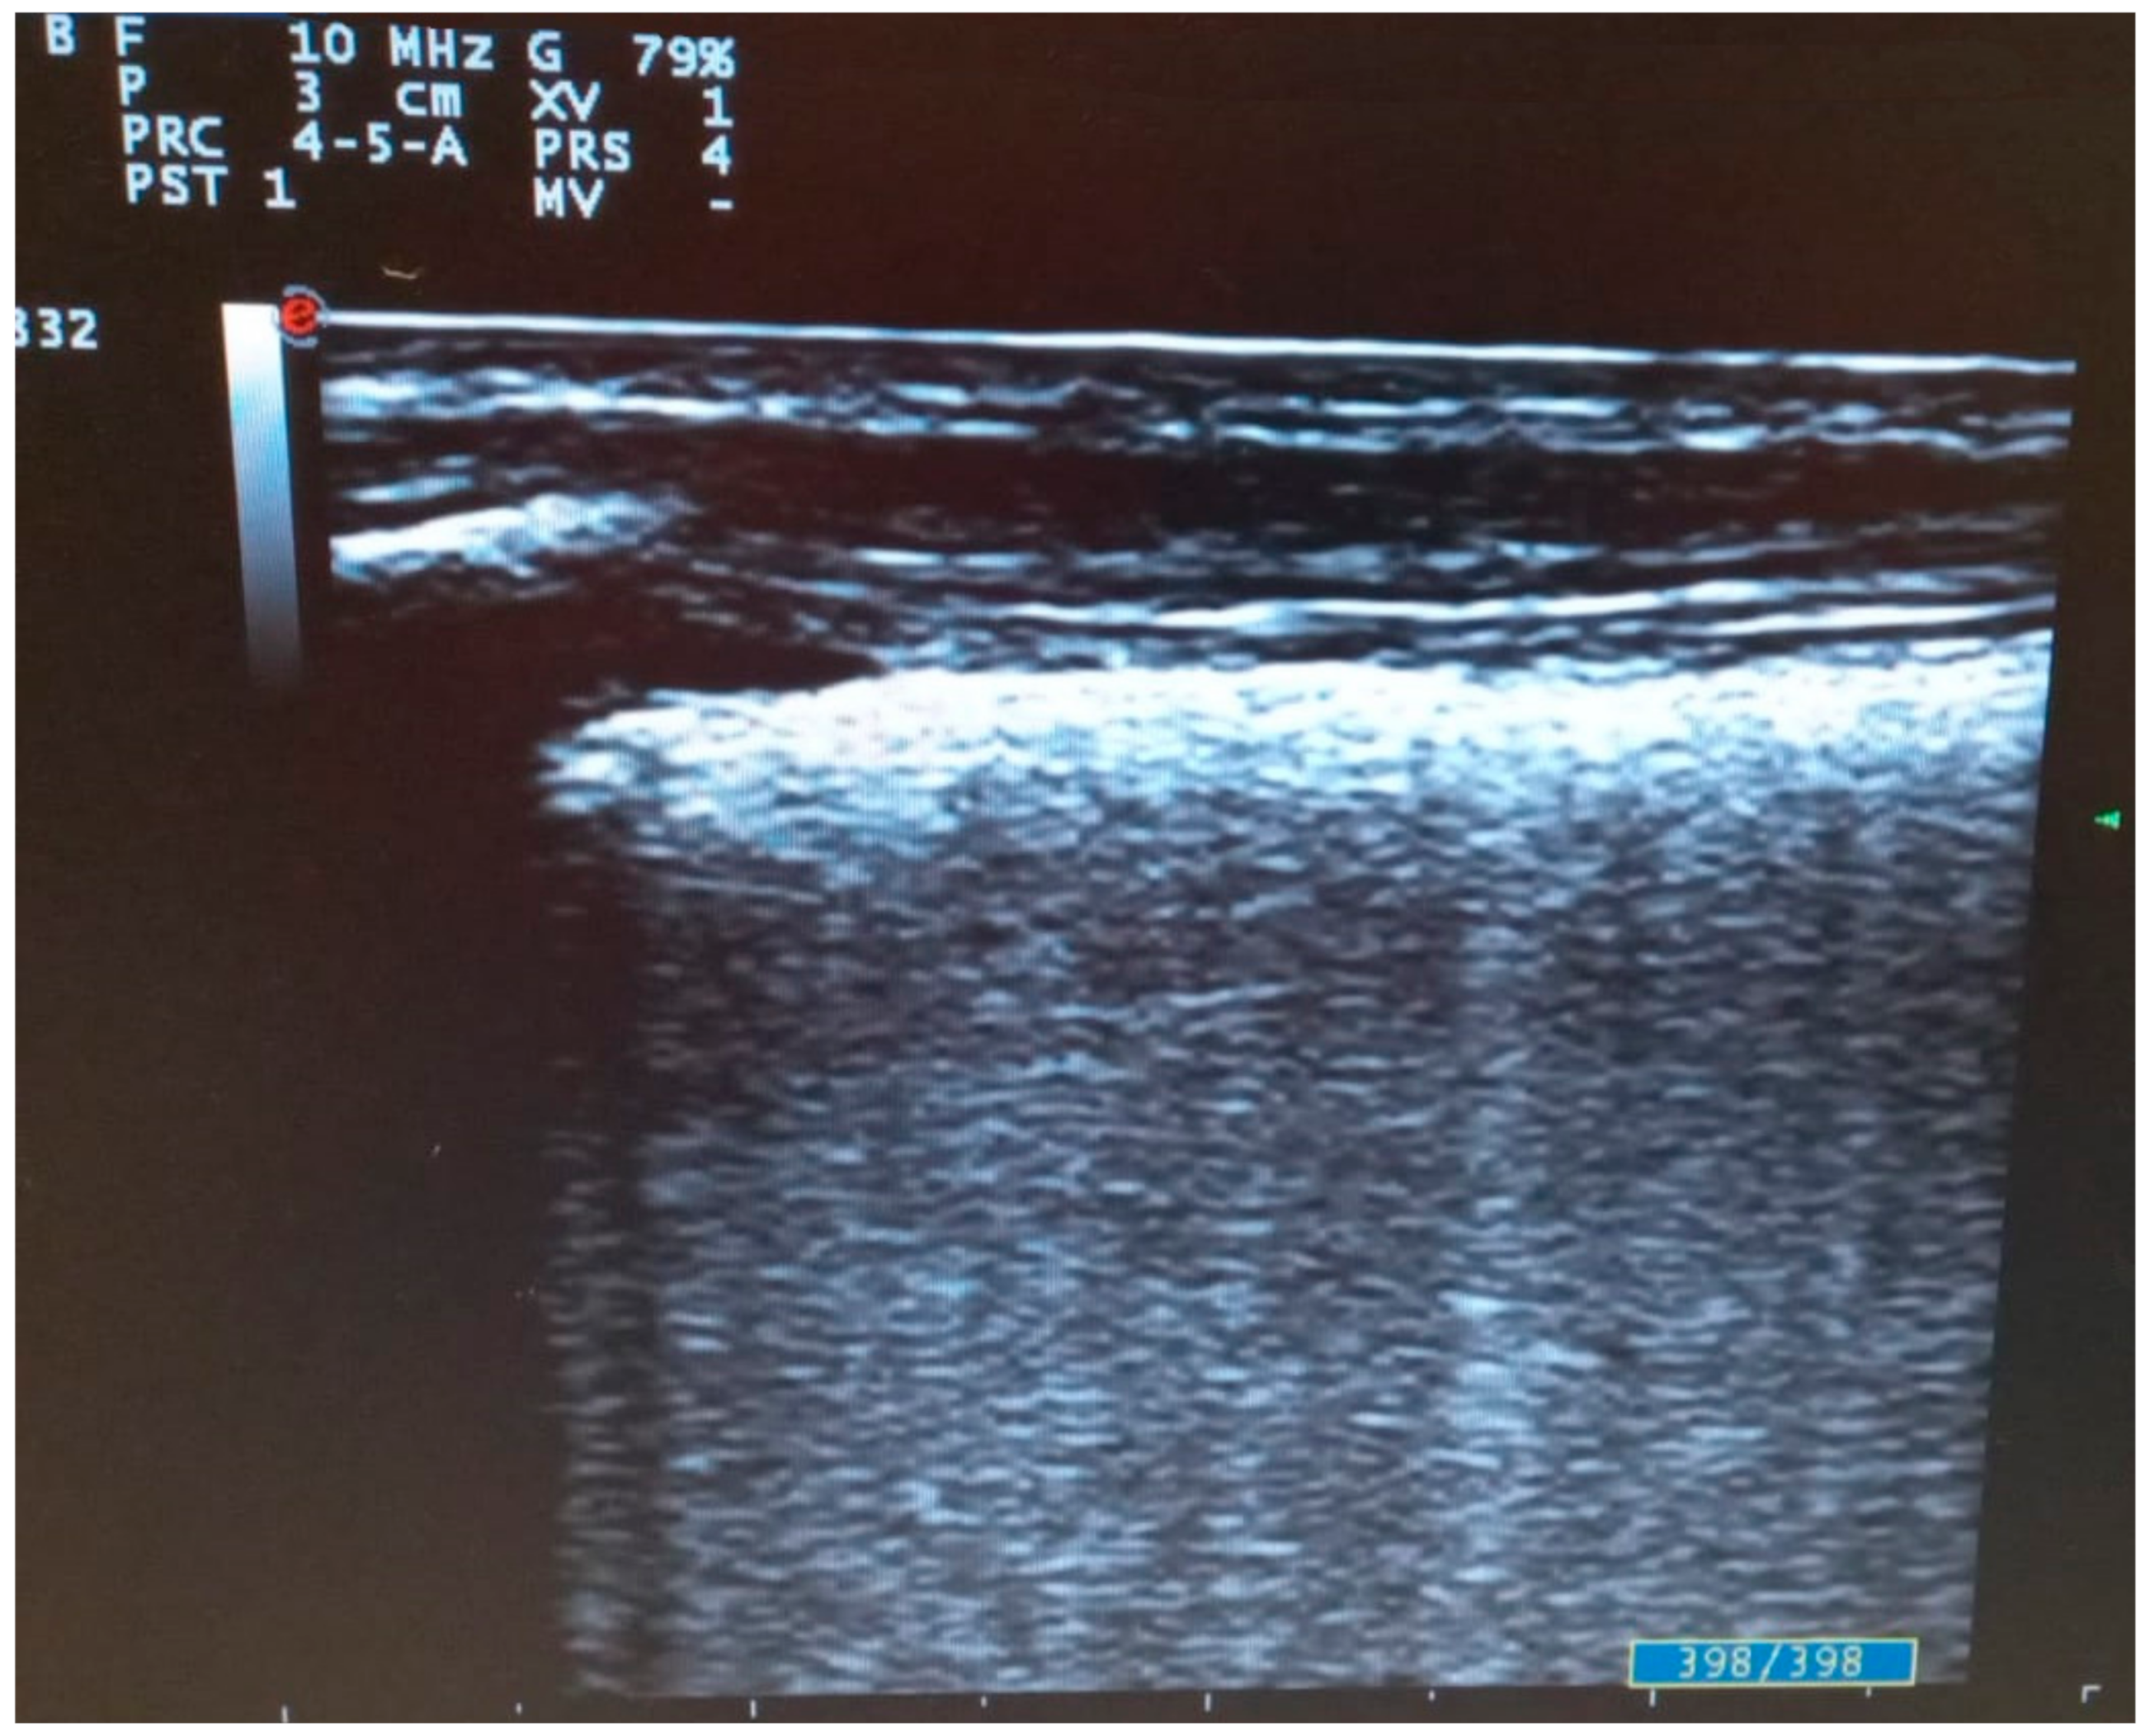

3. Lung Ultrasound in COVID-19 Pneumonia: Findings